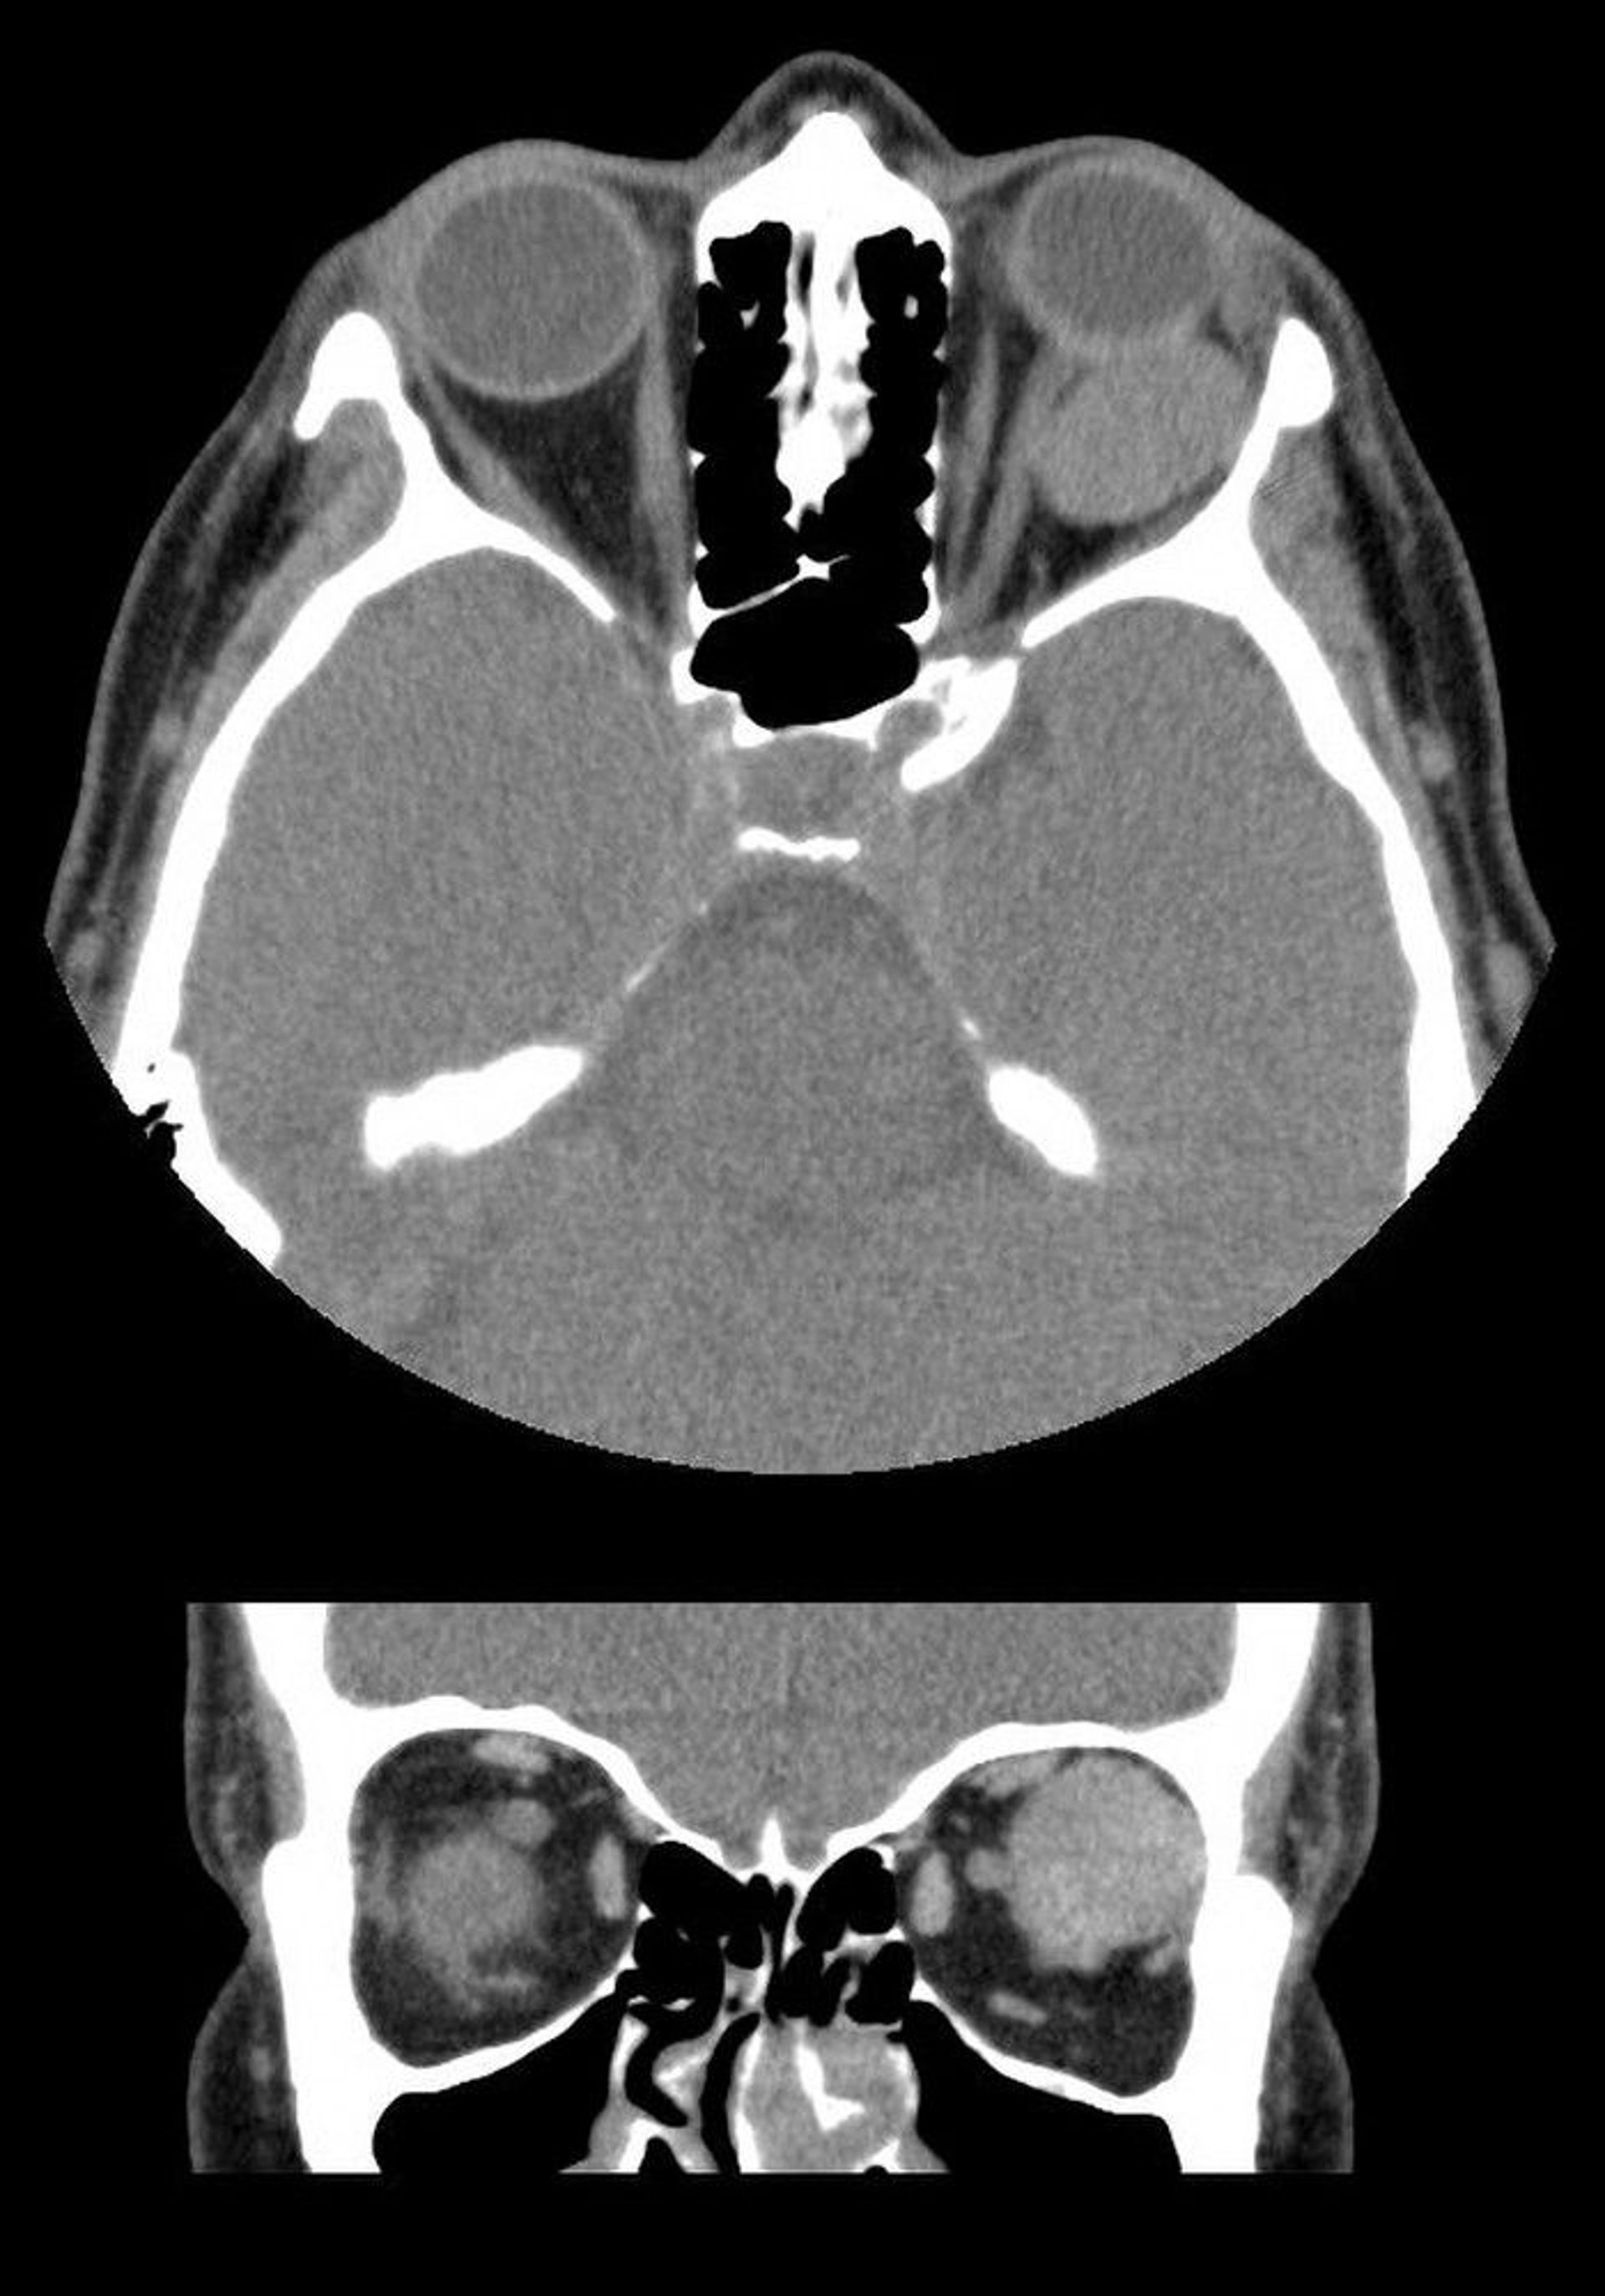

この画像では,CTの水平断像(上)と冠状断像(下)で,左眼球の後方に境界明瞭な眼窩腫瘍が認められる。この腫瘤は海綿状の静脈奇形である。

Images courtesy of James Garrity, MD.